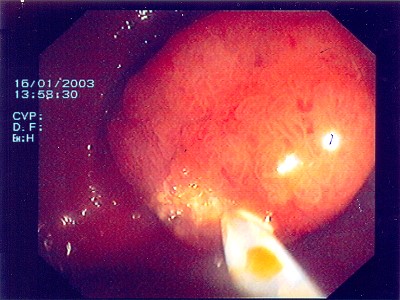

Gut sichtbarer Blutstrahl nach Abtragung eines Polypen

Sichere Blutstillung durch einen Metallclip